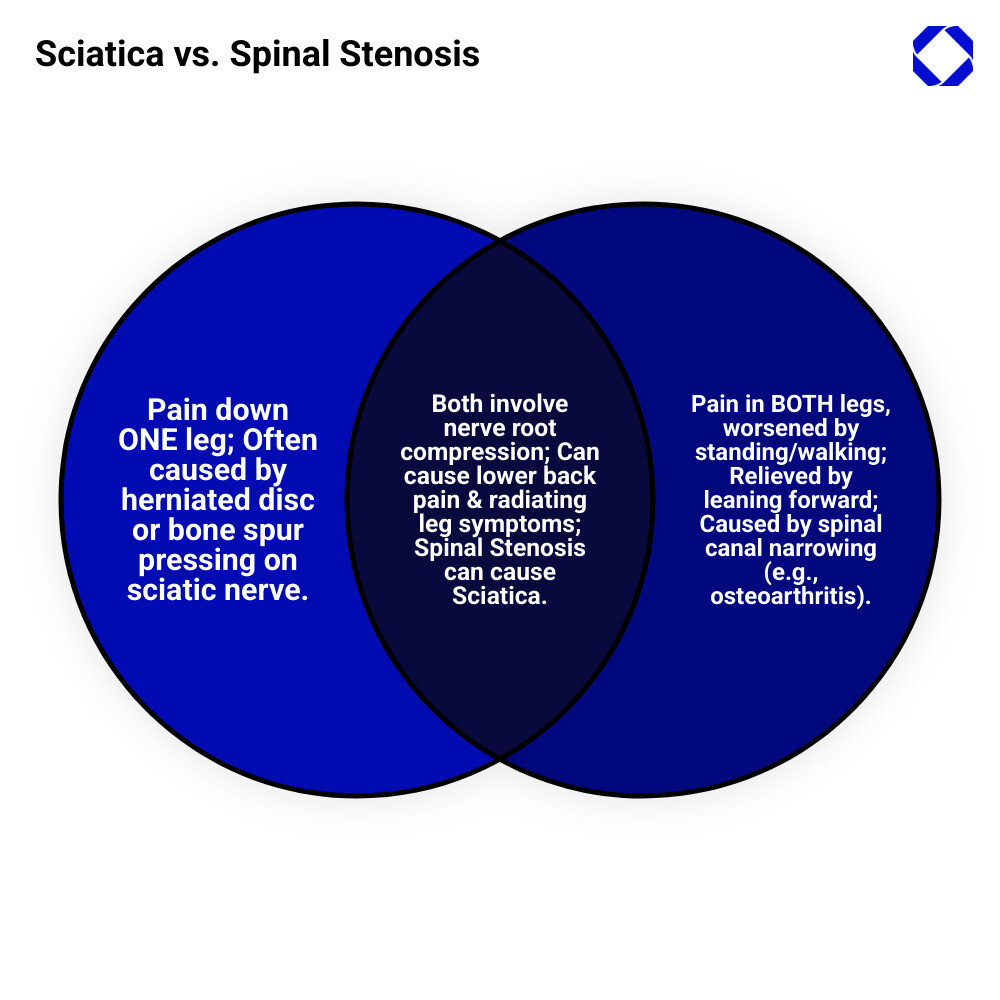

Back pain / sciatica / spinal stenosis are among the most common reasons people seek medical care. If you have lower back discomfort that radiates down your leg, or pain that worsens when you stand, you’re not alone. Understanding the difference between these conditions is the first step toward relief.

The confusion is understandable, as all three can cause lower back pain and make daily activities challenging. However, they have different causes, symptoms, and require different treatments.

Sciatica occurs when something like a herniated disc or bone spur presses on the sciatic nerve, the longest nerve in your body. This creates the characteristic shooting pain down one leg.

Spinal stenosis is a narrowing of the spaces in your spine, often from osteoarthritis or age-related wear. This compresses the spinal cord or nerve roots, typically affecting both legs.

Interestingly, spinal stenosis can cause sciatica. When the spinal canal narrows and puts pressure on sciatic nerve roots, you may experience sciatica-like symptoms as part of your stenosis.

The hallmark of sciatica is a sharp, shooting pain that starts in the lower back and travels through the buttock down the back of one leg. A key distinction is that sciatica typically affects only one leg.

Spinal stenosis is a structural condition involving the narrowing of the spinal canal. This canal protects your spinal cord and nerve roots. When it narrows, it puts pressure on these delicate structures, unlike sciatica, which is a symptom of nerve compression.

Sciatica vs. Spinal Stenosis: A Head-to-Head Comparison

While both sciatica and spinal stenosis cause back pain and leg discomfort, they are distinct conditions. Understanding these differences is crucial for an accurate diagnosis and effective treatment. Let’s compare them side-by-side:

The table highlights the key differences. Here are some nuances we look for during evaluation:

- One leg vs. both legs: Symptoms in one leg strongly suggest sciatica. If both legs are affected, spinal stenosis is a primary suspect.

- Postural triggers: Sciatica pain can be aggravated by many positions. In contrast, spinal stenosis pain is characteristically relieved by leaning forward (the “shopping cart sign”), which temporarily widens the spinal canal.

To add to the confusion, spinal stenosis can indeed cause sciatica.

This happens when the narrowing in the lumbar spinal canal irritates or compresses the specific nerve roots that form the sciatic nerve. Therefore, sciatica can be a symptom of underlying spinal stenosis, not just a result of a herniated disc.